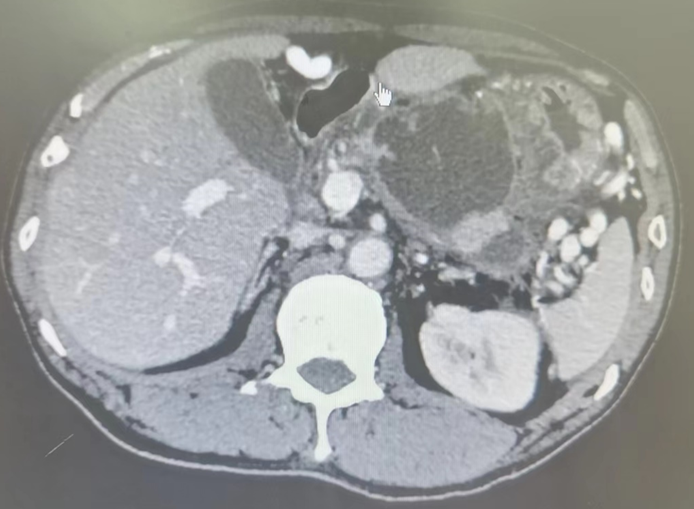

胰腺浆液性囊腺瘤(serouscysticneoplasm,SCN)约占原发性胰腺囊性肿瘤的16%[1],主要好发于中老年女性,且女性发病年龄普遍早于男性,也称为“奶奶瘤”,与胰管不相通[2]。SCN可发生于胰腺的任何位置,其中胰体和胰尾部发生率较高,且有逐年增加的趋势[2-3]。胰腺SCN常见的临床表现为非特异性腹痛,其他症状包括胰胆管梗阻、腹部肿块、乏力、恶心呕吐和体重减轻等,亦有相当比例的患者无症状,为影像学检查偶然发现[2,4]。SCN绝大多数为良性病变,预后良好,极少发生侵袭和转移,死亡率接近0%[5]。临床上对于SCN患者通常选择定期观察随访,只有临床症状明显、病灶较大、生长迅速或无法排除恶性可能的SCN才考虑手术切除[5-6]。SCN是一种预后良好的胰腺良性肿瘤,无症状患者通常无需采取手术治疗[4]。随着医学影像辅助检查的发展,胰腺囊性病变的检出率日益增加[12],因此提高术前影像诊断准确率,规避手术的创伤与风险变得日益重要。在临床实践中,常因SCN影像学表现不典型而无法排除其他具有恶变潜能的肿瘤,如MCN、IPMN、pNET等。CT和MRI是诊断胰腺囊性病变最常用的影像检查方法,PET-CT、EUS、超声造影、EUS-FNA也对诊断具有辅助价值。微囊型是SCN最常见与典型的影像学形态表现[2,14],纤维瘢痕、中央钙化和周围血管改变是诊断SCN的特异性CT征象,有助于与MCN、IPMN的鉴别诊断[15]。但SCN在CT中表现多样,部分病例缺乏钙化、纤维瘢痕等典型特征,而部分则可能出现类圆形、单囊型外观,或有分隔增厚、胰管扩张、胰腺实质萎缩等不典型表现,可能是术前误诊的重要原因[1]。(文献来源:王端,吴东,戴梦华,等.胰腺浆液性囊腺瘤手术切除患者172例的临床及影像学特征分析.中华胰腺病杂志,2024,24(01):33-38.DOI:10.3760/cma.j.cn115667-20230930-00036)浆液性囊腺瘤是良性肿瘤,常见于60岁以上的女性,恶变率极低,整体恶变率低于1%[18,19]。肿瘤生长过程中会压迫邻近器官,有时为了控制症状仍需要切除,尤其是年轻患者;如肿瘤最大径>10cm,建议手术切除,因为患者生存期长,肿瘤生长过程中可能会产生压迫症状或与血管致密粘连包裹,导致肿瘤不可切除。大部分浆液性囊腺瘤生长缓慢且无症状,所以如能获得明确诊断,不需要定期随访。(文献来源:楼文晖.对胰腺囊性肿瘤诊治中几个问题的思考[J].中华外科杂志,2024,62(10):909-912.)SCN是一种良性肿瘤,其特征是成簇的微小囊肿,这些囊肿的隔膜含有丰富的血管。恶性肿瘤的风险极低[9]。然而,对于大小超过4cm的肿瘤或因可能出现恶性肿瘤或症状表现(如腹痛、饱胀和黄疸)而快速生长的肿瘤,建议切除[10,11]。SCN偶尔会长得非常大,并与周围组织形成严重的炎症粘连,使手术作和解剖复杂化[12]。SCN的特点是恶性潜能极低[9]。对于肿瘤超过4cm、表现出可疑的恶性肿瘤特征、表现出快速生长(每年>4mm)或引起症状,可考虑手术切除[10,11]。巨大的SCN会诱发严重的炎症和粘连,压迫多个周围器官和组织,从而使手术干预复杂化。在某些情况下,切除邻近器官和主要血管(如结肠和门静脉)对于切除大SCN是必要的[12,17\u201219]。Liu等[12]报道了6例巨型SCN手术病例。在一个例子中,胰十二指肠切除术由于门静脉广泛受累而导致切除不完全,需要术中修复。另一例病例需要部分切除横结肠,因为肿瘤粘连牢固[12]。此外,巨型SCN通常会形成大量动脉供血器,导致脆弱的静脉结构扩张并使胰腺切除术复杂化。本病例中的肿瘤有两条原发性供血动脉:部分栓塞的GDA和完全栓塞的DPA。这种方法有效地防止了肿瘤扩张,缩小了扩大的引流静脉的大小,便于手术治疗。事实证明,进入肿瘤背侧的DPA栓塞至关重要,因为该区域最初难以进入。此外,在SMA线上方横切胰腺并将肿瘤从脾静脉向胰头分离,尽管门静脉分支晚期受伤,但仍可以安全、完全切除。考虑到胰十二指肠切除术对此类高血管分布肿瘤的复杂性,术前栓塞是巨型SCN的有效管理策略之一。高血管性胰腺肿瘤的术前动脉栓塞术可能会控制术中大量出血的风险,从而可能促进良好的术后病程。鉴于肿瘤难以管理、广泛的血管分布和严重的炎症粘连,巨型SCN的胰十二指肠切除术可能具有挑战性。采用IR进行术前流入控制是大型高血管性胰腺肿瘤有价值的胰腺切除术策略之一。(文献来源:MatsuyoshiT,IkenagaN,NakataK,OkamotoD,MatsumotoT,AbeT,WatanabeY,IdenoN,KakuK,FujimoriN,OhuchidaK,OkabeY,OdaY,IshigamiK,NakamuraM.Acaseofpreoperativeembolizationforagianthypervascularpancreaticserouscysticneoplasminpancreaticoduodenectomy.SurgCaseRep.2024Sep6;10(1):208.)